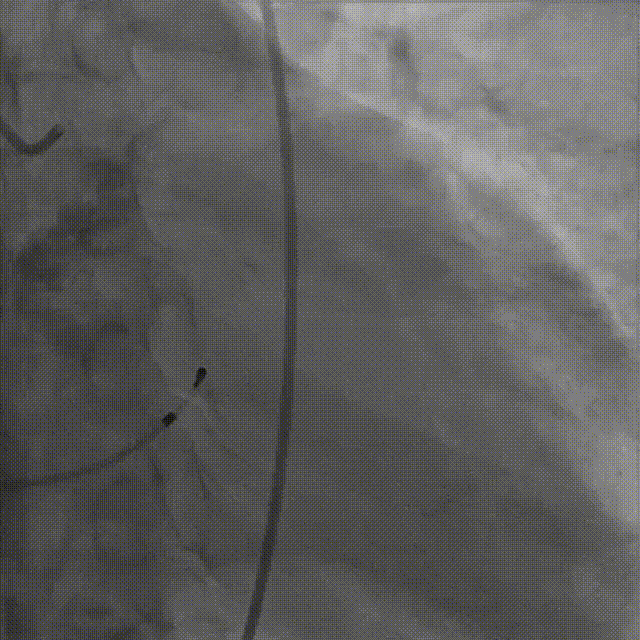

主动脉根部造影,狭窄伴反流

导丝顺利跨瓣

23mm球囊预扩无腰征,微量漏

输送器柔顺过弓、跨瓣

瓣膜开始零位定位

瓣膜逐步释放到工作位

工作位造影位置良好

瓣膜逐个脱钩

完全释放后造影,膨胀不良,有漏

25mm球囊后扩

后扩后瓣膜形态良好,造影基本无漏